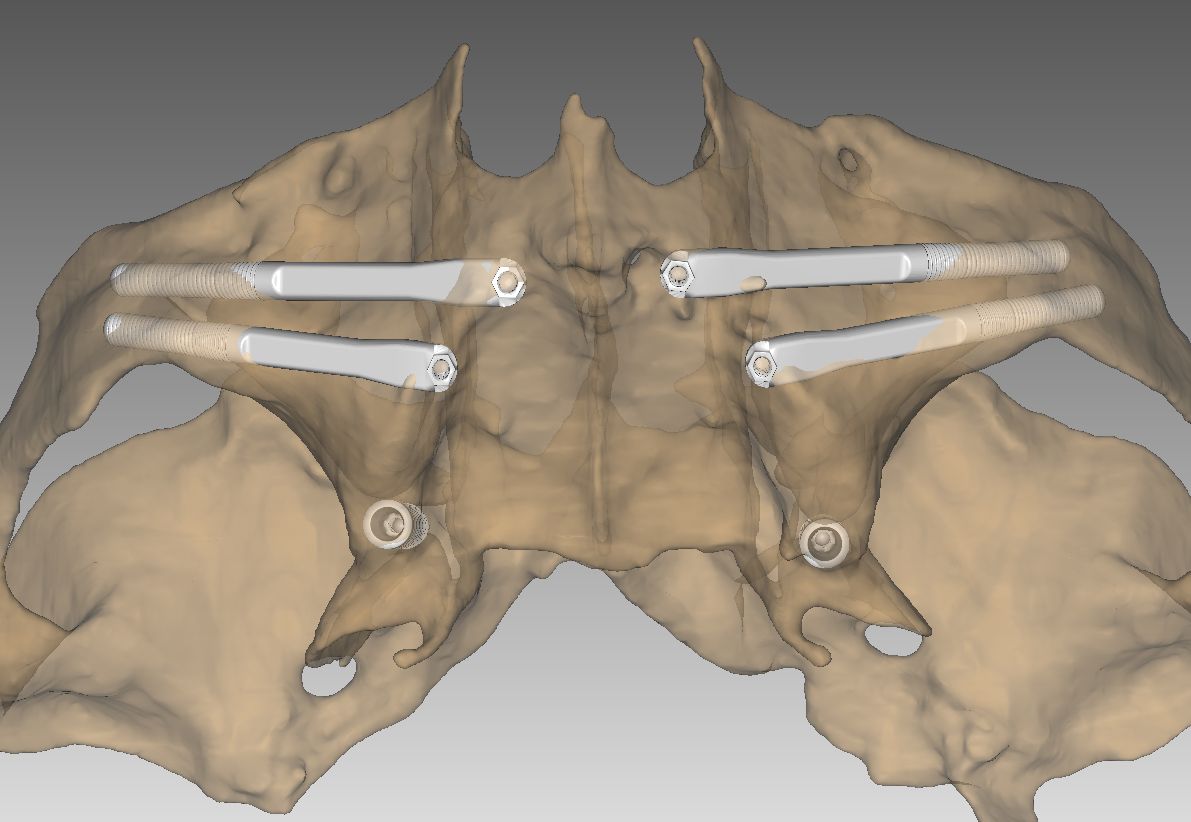

1. Implantes Cigomáticos

Son implantes más largos que se fijan en el cuerpo del hueso cigomático (pómulo). Son la «regla de oro» para tratar maxilares totalmente atróficos. Permiten colocar una arcada completa de dientes fijos sin necesidad de realizar injertos de cadera o calota craneal, reduciendo drásticamente la morbilidad del paciente.

Se anclan en estructuras del esqueleto facial como el hueso cigomático (pómulo), la apófisis pterigoidea o la región transnasal. Al fijarse en este «hueso basal» o cortical, garantizamos una estabilidad mecánica superior desde el primer día.

- Planificación digital y cirugía guiada para máxima precisión.